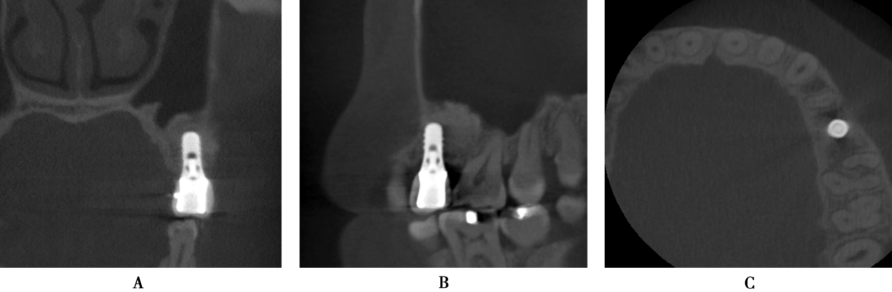

术前CBCT示剩余牙槽骨高度约3mm,近远中距离约10mm,宽度大于8mm,上颌窦内清澈无炎症,上颌窦底黏膜约2mm(图1B,C)。为保证植骨效果,拟进行上颌窦侧壁开窗外提升并同期植入种植体。

图1 A6缺失,CBCT示剩余牙槽骨高度3mmA.口内观;B.矢状面;C.冠状面